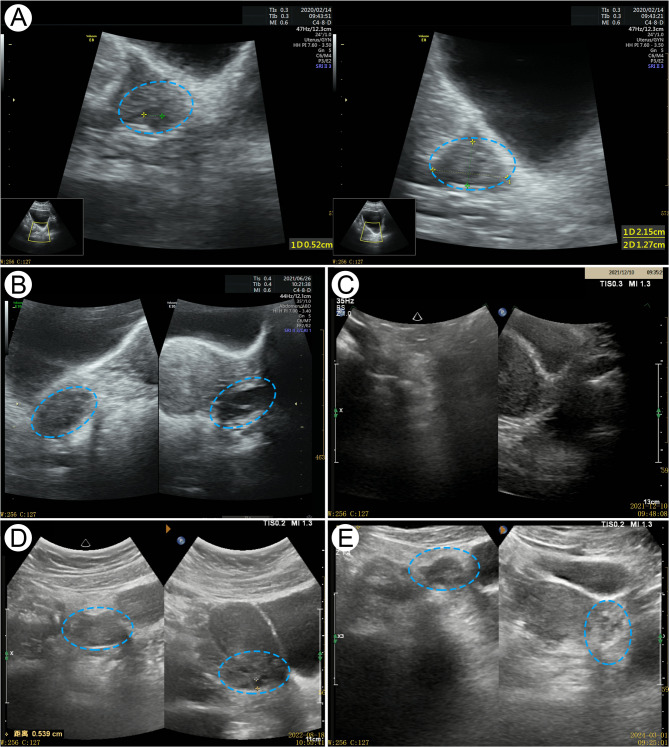

Case presentation: Here, we report a case of a 13-year-old female with 2-year menstrual disorder. The anti-mullerian hormone (AMH) levels were test twice, with interval of 2 months, yielding results of 0.41 ng/mL and 0.50 ng/mL, respectively. Colour Doppler ultrasound examination showed that there were 4-6 antral follicles bilaterally. The patient was diagnosed with DOR. She was treated with Heyan Kuntai capsule (HYKT) combined with hormonal therapy (HT). Post treament, her AMH level, follicle stimulating hormone level and AFC normalized. Discontinuation of HYKT and continuation of HT alone for 5 months proved ineffective. Consequently, HYKT in combination with HT was continued, leading to normal ovarian reserve function restoration. No adverse reactions were observed during the 4-year follow-up.